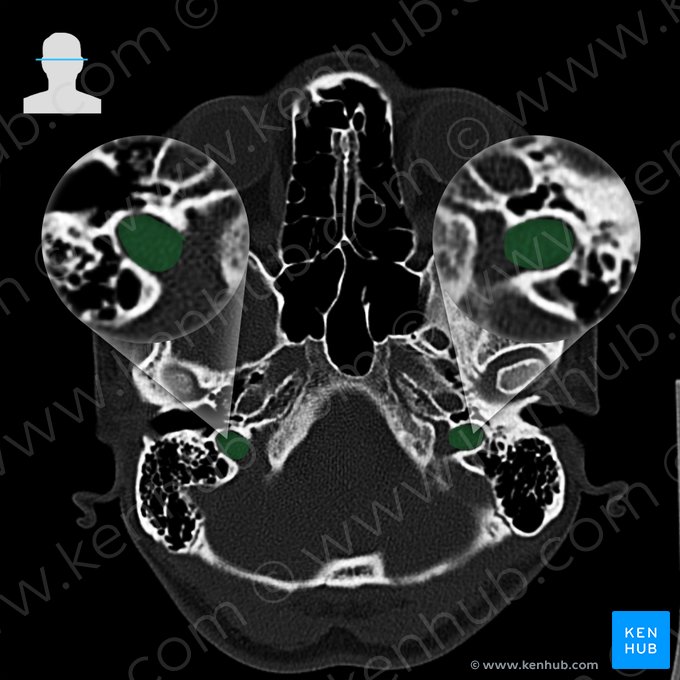

Bones of the head (CT)

Due to being highly saturated with calcium, the bones have the highest density on CT scans. Thus, they appear as white on scans. This enables us to evaluate the integrity of the bones, examine them for fractures, dislocations, osteolytic processes and dysplasia.

The following images will present you with the most important bony landmarks of the head and neck seen at the levels of jugular fossa, atlas (C1) and axis (C2).